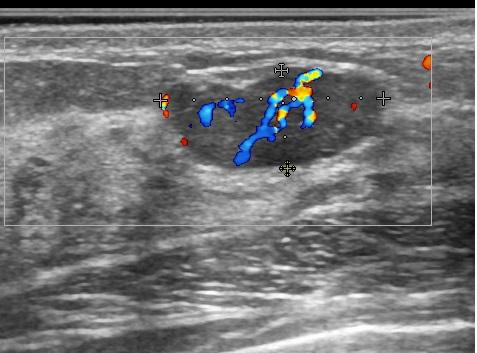

Допплеровский режим определяет кровоток. Важная технология, которая позволяет врачу увидеть сосудистую сеть патологического образования без введения контрастного вещества. Конечно, Допплер не такой чувствительный режим, как контрастирование, но в большинстве случаев он дает важную информацию и способствует раннему выявлению рака.

Рис.9 Эхограмма гиперваскулярной фиброаденомы молочной железы